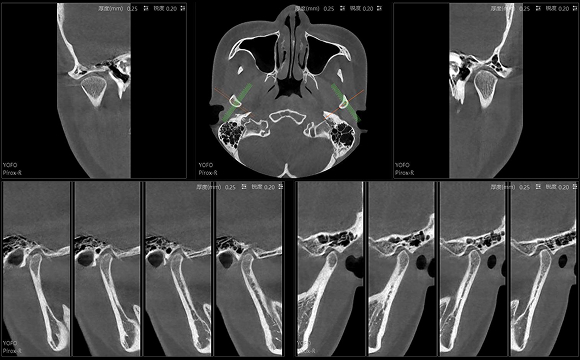

只需一次单圈扫描即可获得CT、3D全景和3D正/侧位影像,并能同时生成3D TMJ视图

提高诊疗效率,避免过度检查,减少患者所受的辐射

• 3D TMJ视图

3D TMJ视图